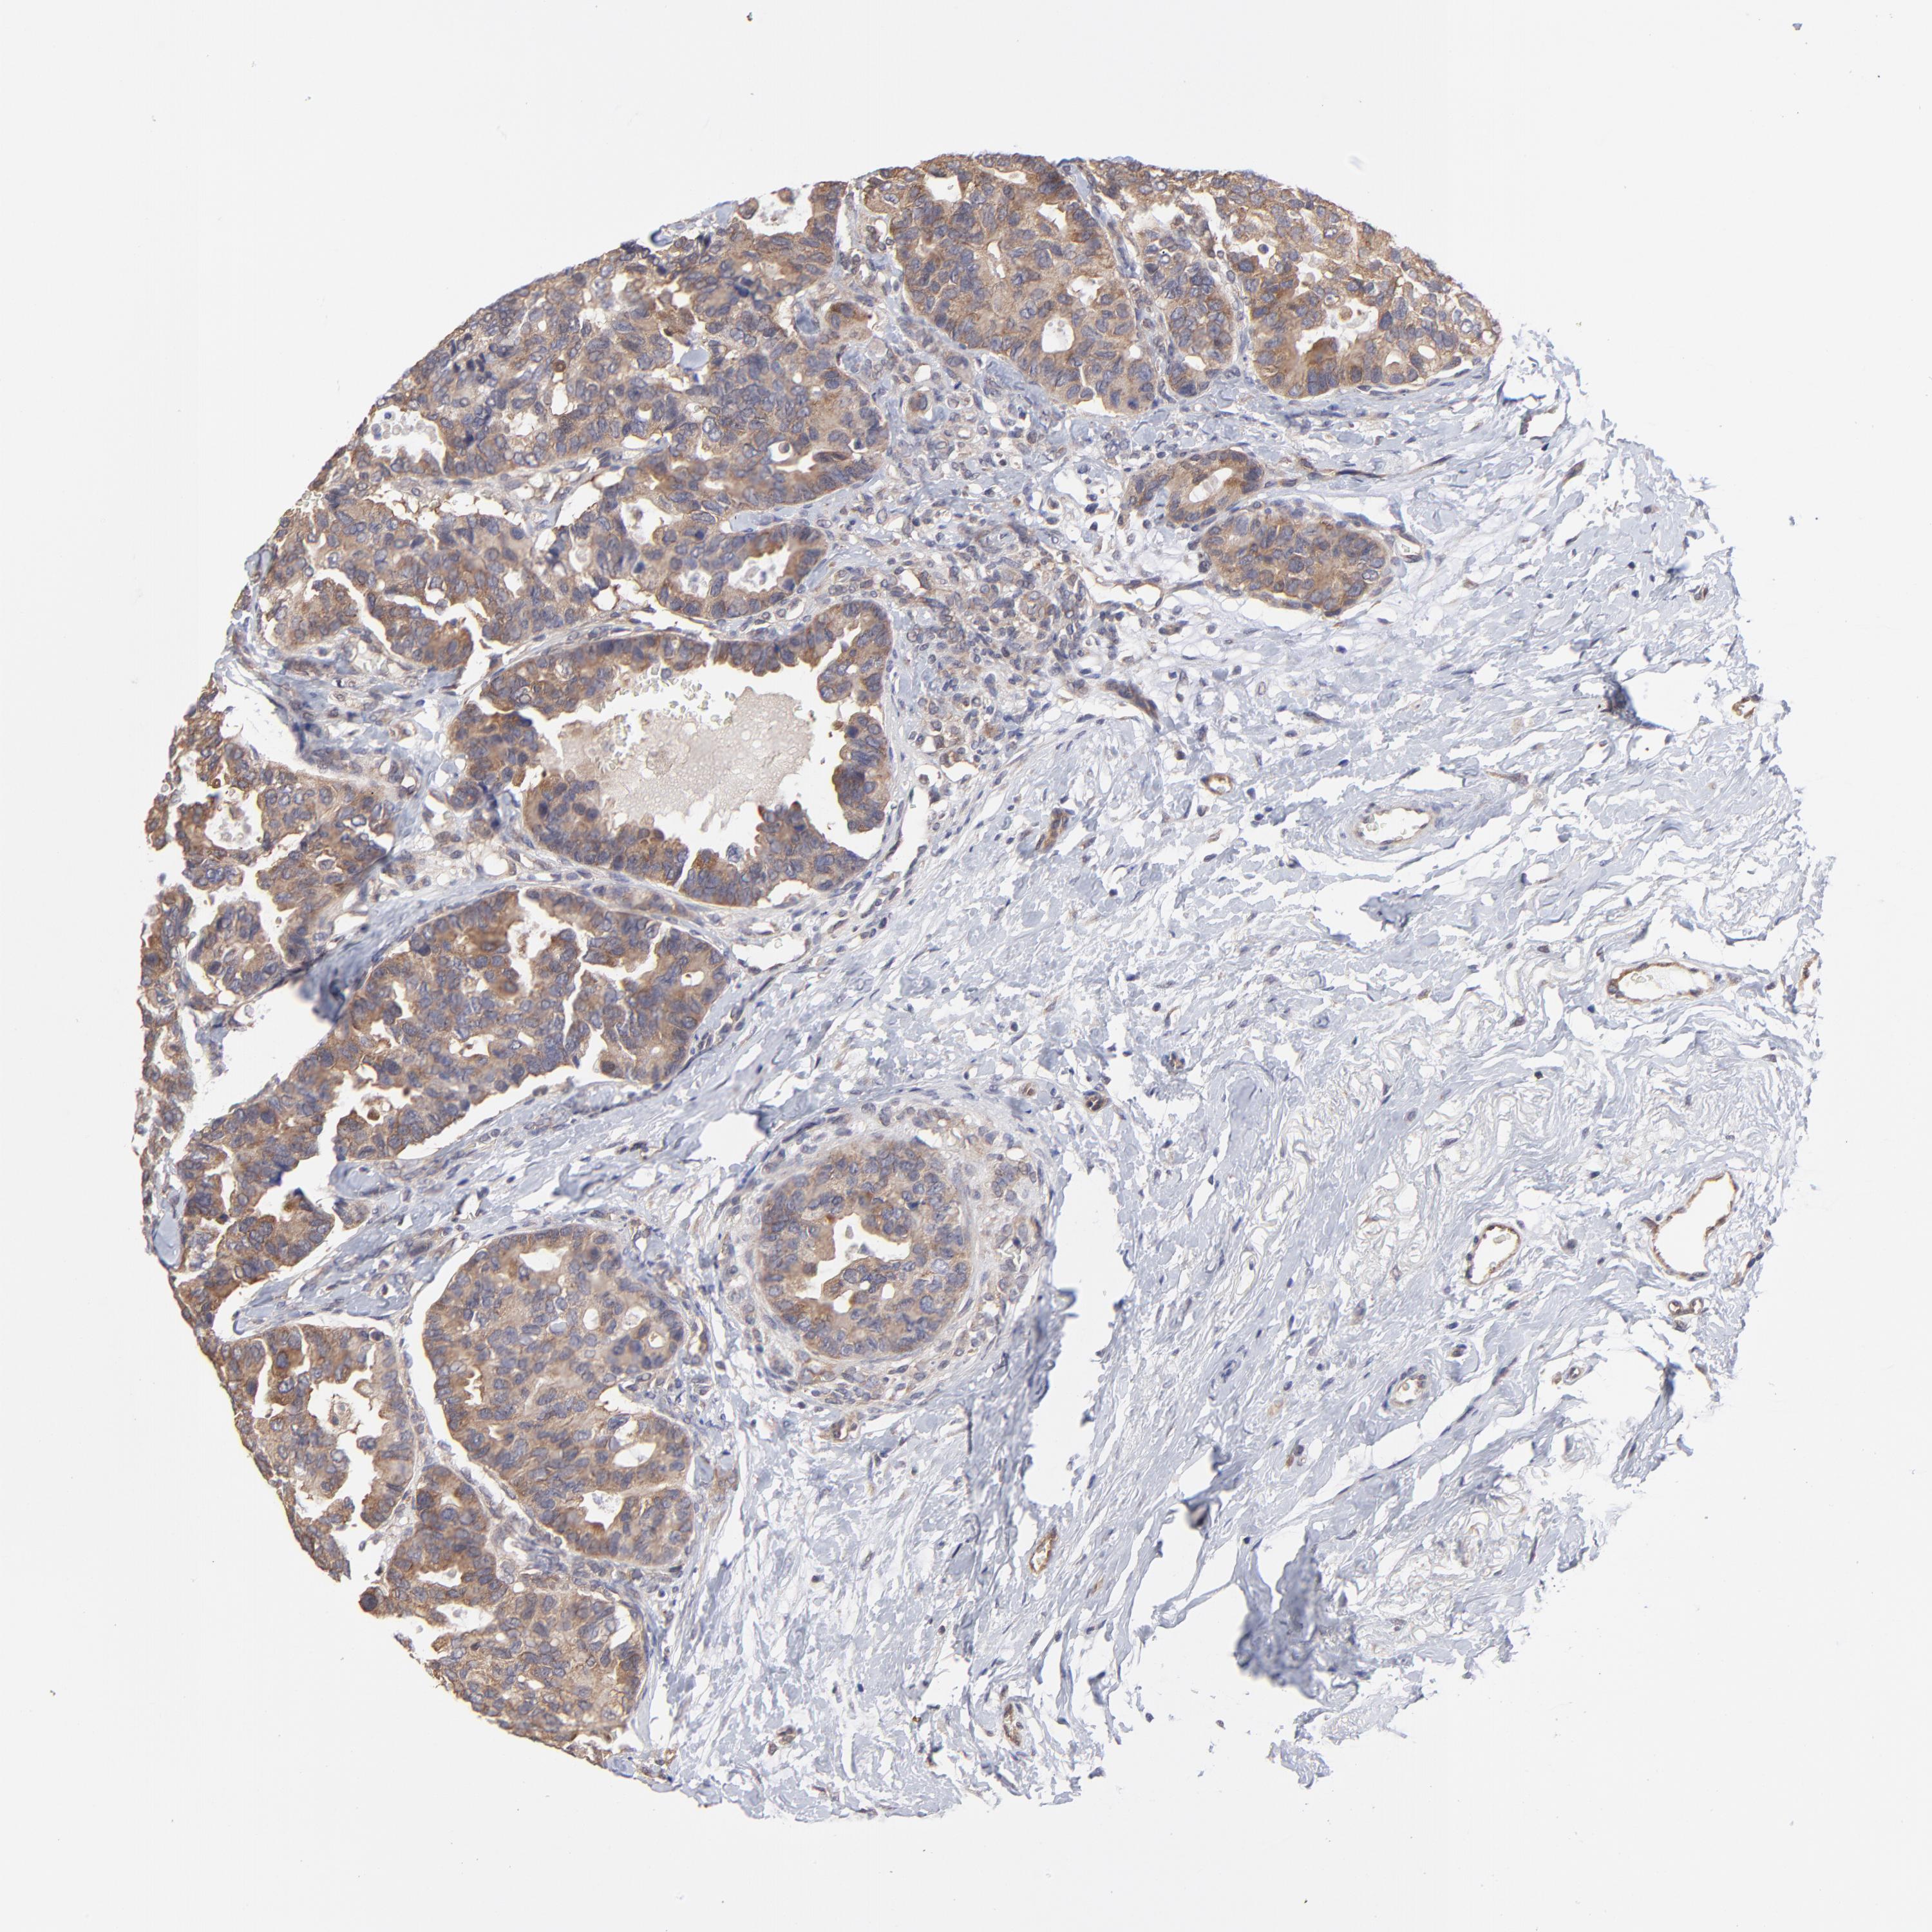

CANCER BREAST CANCER Show tissue menu

BRCA TCGA BRCA VALIDATION PROTEIN EXPRESSION

ANTIBODIES

AND

VALIDATION